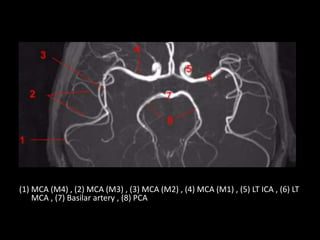

(1) MCA , M4 , (2) MCA (M3) , (3) MCA (M2) , (4) MCA (M1) , (5)

ICA (LT side) , (6) MCA (LT side)

(1) MCA (M4) , (2) MCA (M3) , (3) MCA (M2) , (4) MCA (M1) , (5) LT ICA , (6) LT

MCA , (7) Basilar artery , (8) PCA